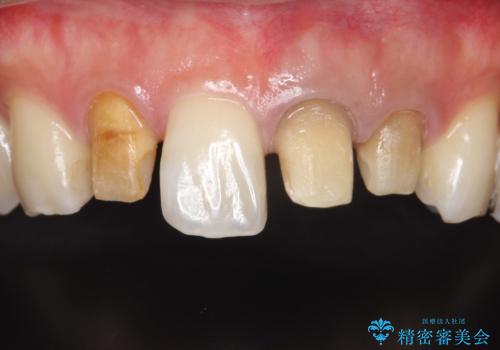

歯並びを含めて前歯をきれいにしたい インビザラインとセラミック治療

- 全体的なガタガタと前歯をきれいにしたいとのことで来院されました。

下の歯は重度のガタガタがあり、上の前歯は何本かが神経の治療がしてある状態でした。

インビザラインにて歯並びを整え、上顎の前歯にセラミックを装着する計画としました。